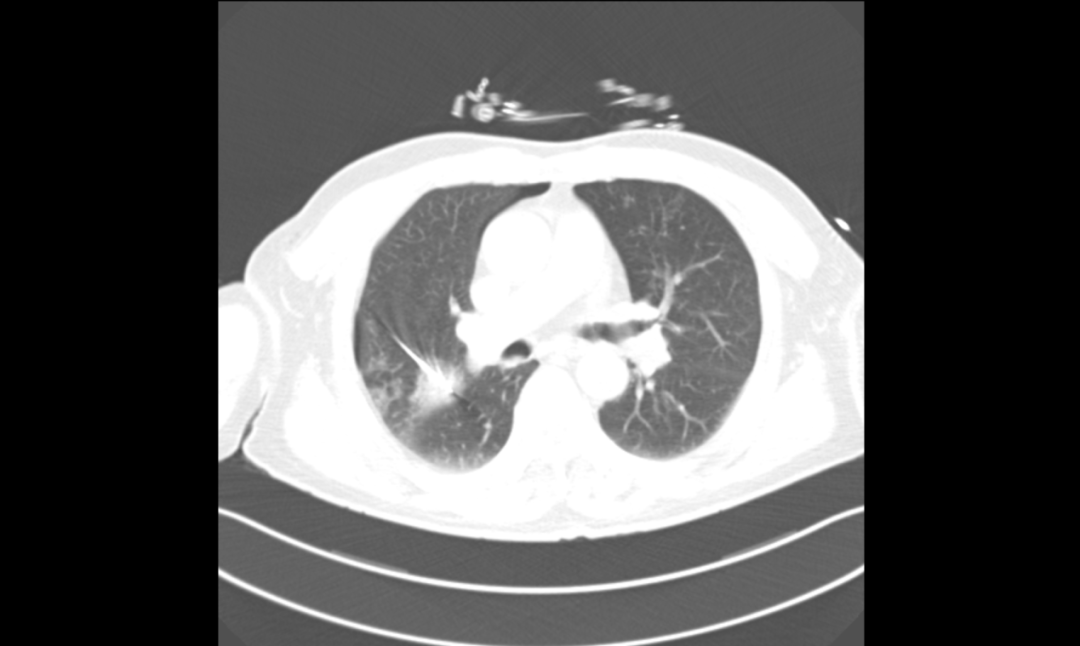

▲微波消融术后复查胸部CT

在罗少华主任统筹下,省医派驻专家时丰主任带领呼吸介入团队于5月28日为患者成功实施了微波消融术。手术过程中,我们密切监测患者的生理参数,确保治疗的安全性。经过精心治疗与护理,患者已顺利出院,目前病情稳定,恢复状况良好。